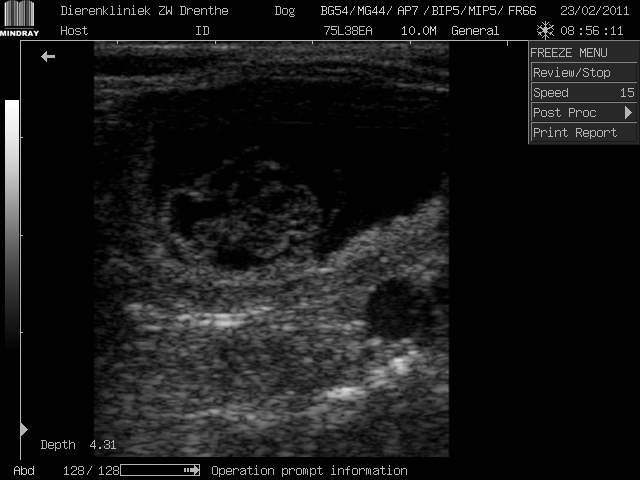

Even een kleine update, het gaat erg goed met ons moedertje. Ze krijgt al een flinke buik en eet als een grote. Ik heb echofoto's op mijn profiel geplaatst maar weet alleen niet hoe ik ze hier krijg. Nog drie weekjes geduld pfff

Deze bedoel je zeker? Ik plaats hem meteen maar even.

Ik (als leek) vind het een bescheiden buikje maar ze was natuurlijk nog niet heel ver en is ook niet groot van formaat.

Deze bedoel ik inderdaad, ze was hier 5 en een halve week en normaal heeft ze een middel

. Dank je wel voor het plaatsen